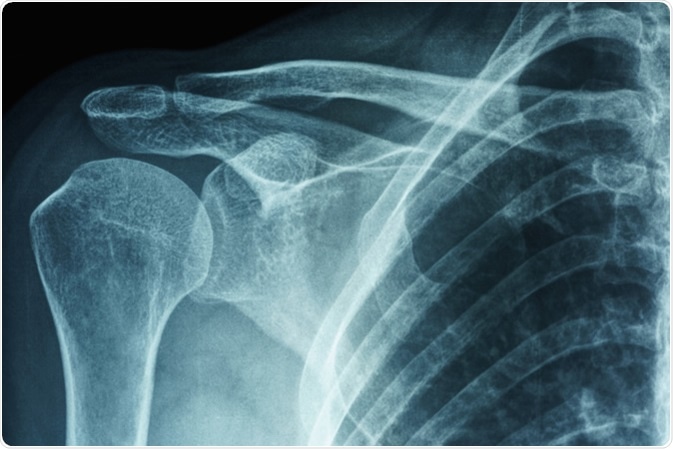

Frozen Shoulder

A frozen shoulder (adhesive capsulitis) is a condition that causes stiffness and pain on the shoulder joint. The signs and symptoms include severe pain, limited range of motion, and stiff shoulder joint. The symptoms begin gradually and worsen over time. It typically resolves within one to three years.

X-ray film of primary frozen shoulder or adhesive capsulitis of Asian female patient. Image Credit: PK289 / Shutterstock